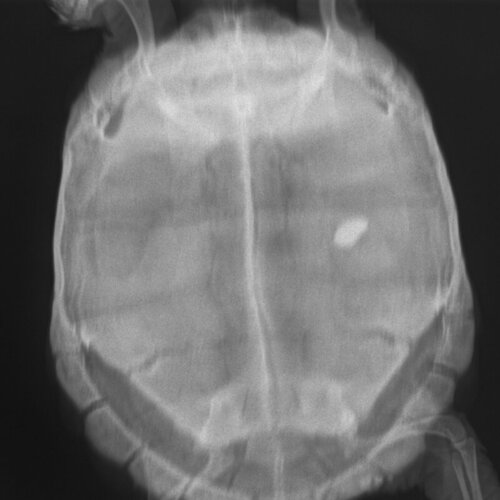

Стул жидкий. Сегодня первый раз за 2 недели вышли соли. Также черепаха очень вялая, двигается только чтобы найти укрытие и сидит там. Так же при купании проявляет активность. На рентгене есть пятно, возможно инородное тело.

9. Обращались в 2 ветклиники БЭСТ и ЭНИМАЛЗ. Делали клизму, рентген и анализ крови. В последней нам сегодня (18.07.2022) сделали укол мелоксивет 0.12 мл разведенный до 0,5 мл натрия хлорида подкожно.

Ренген.JPE